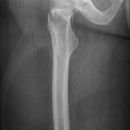

Femurschaftfraktur